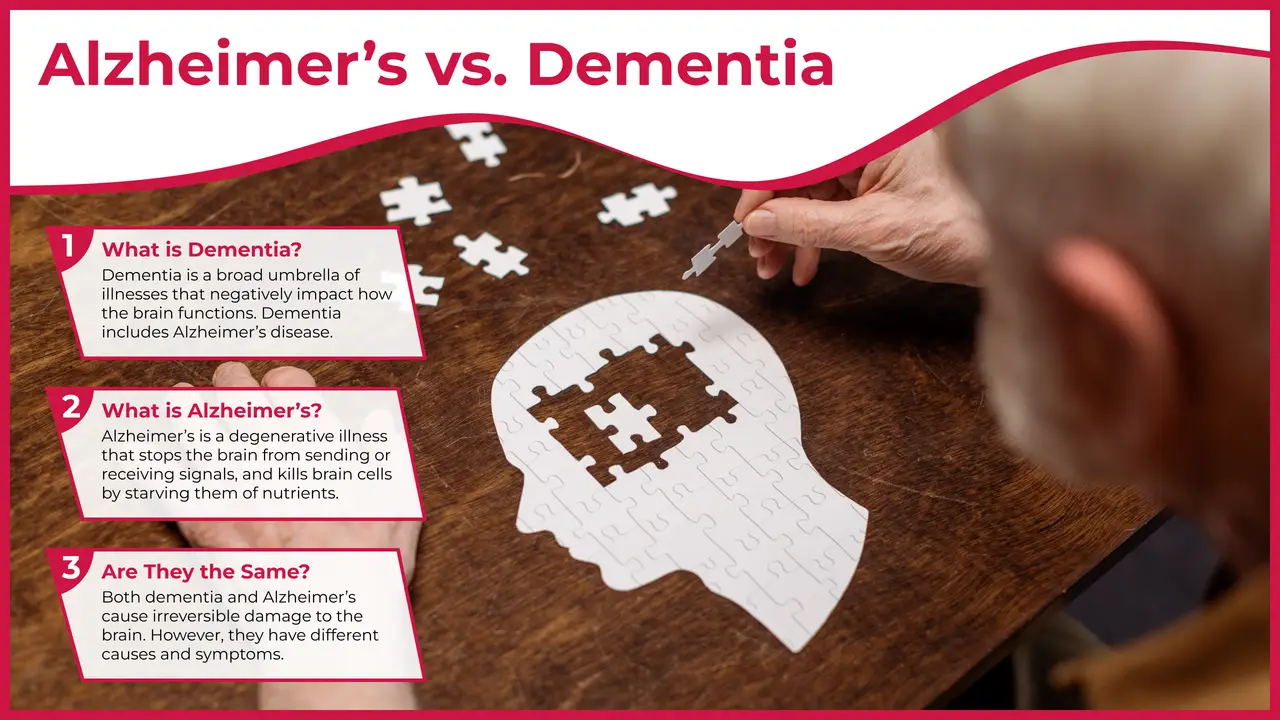

Dementia is a broad term that consists of many conditions with various causes. Alzheimer’s disease is one specific condition and is the most common cause of dementia.

Many times, you may have noticed people using the terms dementia and Alzheimer’s interchangeably. However, they do not particularly mean the same thing. The simplest way to understand them is to think of the term dementia as the broad umbrella under which many different illnesses fall under. One such disease which by far is the most common form of dementia is Alzheimer’s disease.

Dementia is a broad term that is used to describe a group of illnesses that negatively impacts the function of the brain. Some forms of dementia include Alzheimer’s disease, vascular dementia, lewy body disease, alcohol-related dementia, younger-onset dementia and many more. Alzheimer’s disease is a progressive degenerative illness that damages the brain. It is caused by amyloid plaques deposits and neurofibrillary tangles that lead to the death of the brain cells. The amyloid plaques inhibit the brain from sending messages or signals and the neurofibrillary tangles prevent the brain cells from receiving nutrients and energy, resulting in their death. The death of the brain cells causes shrinking of the outer layer of the brain which is the area responsible for memory, language and judgement.